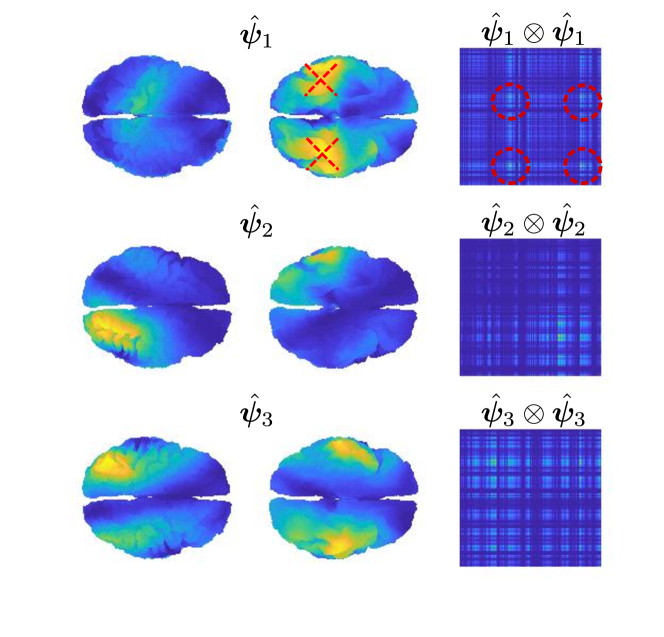

The unregularized version of model (14) is equivalent to a Singular Value Decomposition applied to each matrix independently, which would lead to a set of orthogonal estimates , for each . In the regularized model orthogonality is not enforced, however the estimated PC components can be orthogonalized post-estimation by means of a QR decomposition.

and the associated approximate representation of , in terms of and , is

where is an estimate of the variance and is an estimate of . The tensor product is such that for all . The regularizing terms in (14) introduce spatial coherence on the estimated and thus on the estimated eigenfunctions of , fundamental in an inverse problems setting.

On the one hand, model (16) constrains the estimated covariances to be of the form and not of the more general form . On the other hand, such a model takes advantage of all the samples to estimate the components . Moreover, the associated variables give a convenient approximate description of the th covariance, as they are comparable across samples, as opposed to the one computed from model (14). In fact, the th covariance function can be represented by the variance vector , for a suitable truncation level , where each entry is associated with the rank-one component . For each , a scatter plot of the variances , as the one in Figure 14, helps understand what the average contribution of the th components is and what its variability across samples is. Model (17) could also be interpreted as a common PCA model (Flury, 1984; Benko et al., 2009), as are the estimated regularized eigenfunctions of the pooled covariance .